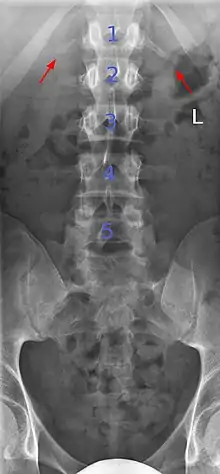

Butterfly vertebrae

Butterfly vertebrae have a sagittal cleft through the body of the vertebrae and a funnel shape at the ends. This gives the appearance of a butterfly on an x-ray. It is caused by persistence of the notochord (which usually only remains as the center of the intervertebral disc) during vertebrae formation. There are usually no symptoms. There are also coronal clefts mainly in skeletal dysplasias such as chondrodysplasia punctata. In dogs, butterfly vertebrae occur most often in Bulldogs, Pugs, and Boston Terriers.[9]

Butterfly vertebra (red). Normal vertebra for comparison (blue).

Volume rendering of a CT scan of the lumbar vertebral column, showing butterfly vertebrae at several levels, most typically in L1.